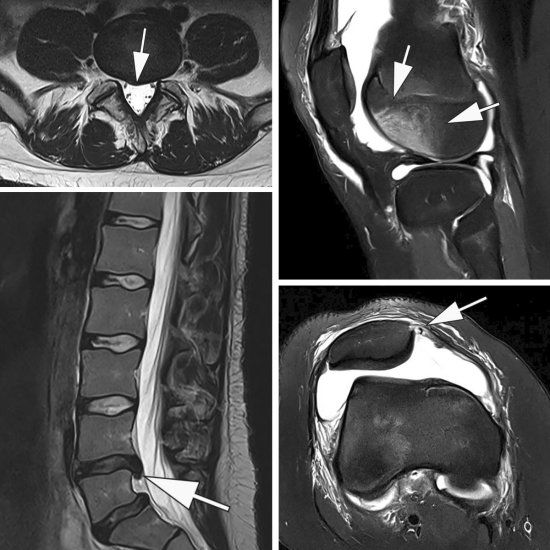

Interview • Shift from biopsy to imaging

Magnetic resonance imaging (MRI) holds great potential to spare men with suspected prostate cancer a painful biopsy. In our interview, Dr. Peter Seidensticker, Head of Medical Affairs Radiology at Bayer, outlines how MRI could be implemented as a ... |